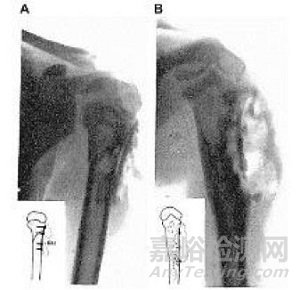

早在1907年,Lambotte就使用鐵絲環(huán)扎術和一塊帶有六個鋼螺絲的鎂板來固定骨折的小腿,但是由于鎂和鐵接觸后發(fā)生電化學反應,加速了鎂的腐蝕,術后一天即觀察到了大量的皮下氣腔,并伴有局部有腫脹和疼痛。因此在排除了鎂和其他金屬混用后,Lambotte與其助手Jean Verbrugge用鎂釘治愈了4例兒童肱骨髁骨折(圖1),除發(fā)現(xiàn)氣泡產(chǎn)生外,沒有其它不良反應發(fā)生。Jean Verbrugge在接下來的幾年里,采用鎂及其合金(AZ63和Mg-8wt.%Al)進行了25例骨折治療的臨床實驗,如圖2所示。由于鎂在植入后的快速腐蝕降解,鎂板和鎂釘固定系統(tǒng)植入三周后,骨折線即消失不見。除此之外,有病人反映,植入部位會有暫時的麻木感覺,但沒有組織感染跡象或不良反應發(fā)生。在這些病例中,因植入尺寸以及位置不同,鎂在人體內在三個星期到一年最終吸收。McBride進行的臨床應用探索,如圖3所示,發(fā)現(xiàn)鎂可以加速治療初期結締組織的早期增殖和愈合組織的增生。1940年,Maier使用了由梭形鎂片制成的針治療肱骨骨折,并且在接下來的14年獲得良好的恢復。

圖2 A, B為采用鎂板和鎂釘為兒童的踝部骨折進行固定,(A)術后X光顯示有氣泡形成;(B)鎂板術后3周已基本腐蝕降解。(C)為采用鎂釘治療兒童髁部肱骨骨折的術后X光照片,顯示植入早期皮下有氣泡形成。

圖3 McBride采用Mg-Mn合金做成薄的帶角度的板和螺釘獲得無旋轉扭曲的骨愈合效果。